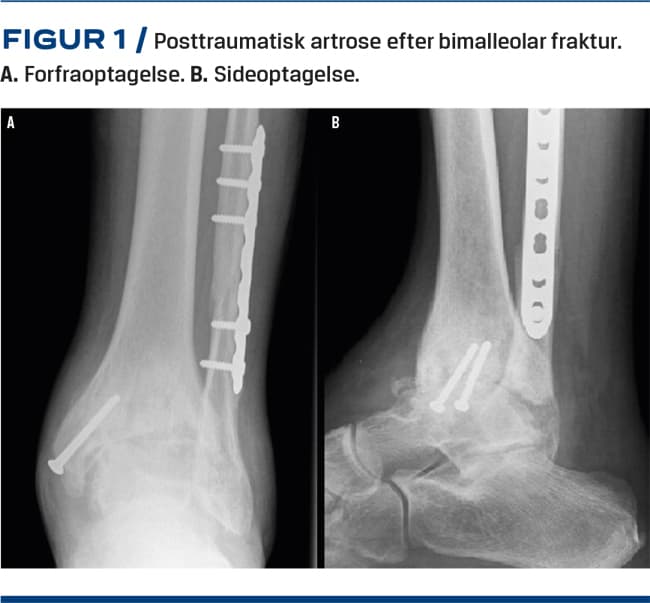

Røntgenbilleder af ankelleddet tages altid med belastning og viser typisk ledspalteafsmalning, subkondral sklerosering, eventuel fejlstilling (i både frontalt og sagittalt plan), osteofytter, påvirkning af syndesmosen eller andre tegn på tidligere frakturer. Se Figur 1 for typiske fund ved posttraumatisk artrose. Supplerende billeddiagnostik i form af CT, vægtbelastet CT, SPECT og MR-skanning kan bidrage med yderligere information. MR-skanning er den mest sensitive og specifikke noninvasive undersøgelse til vurdering af brusken i ankelleddet, mens SPECT-CT gør det muligt at korrelere morfologiske og biokemiske informationer i udredning af ankelartrose og kan hjælpe til at lokalisere isolerede læsioner i ankelleddet [7]. Figur 2 er en oversigt over udredning, visitation og behandling i Danmark.